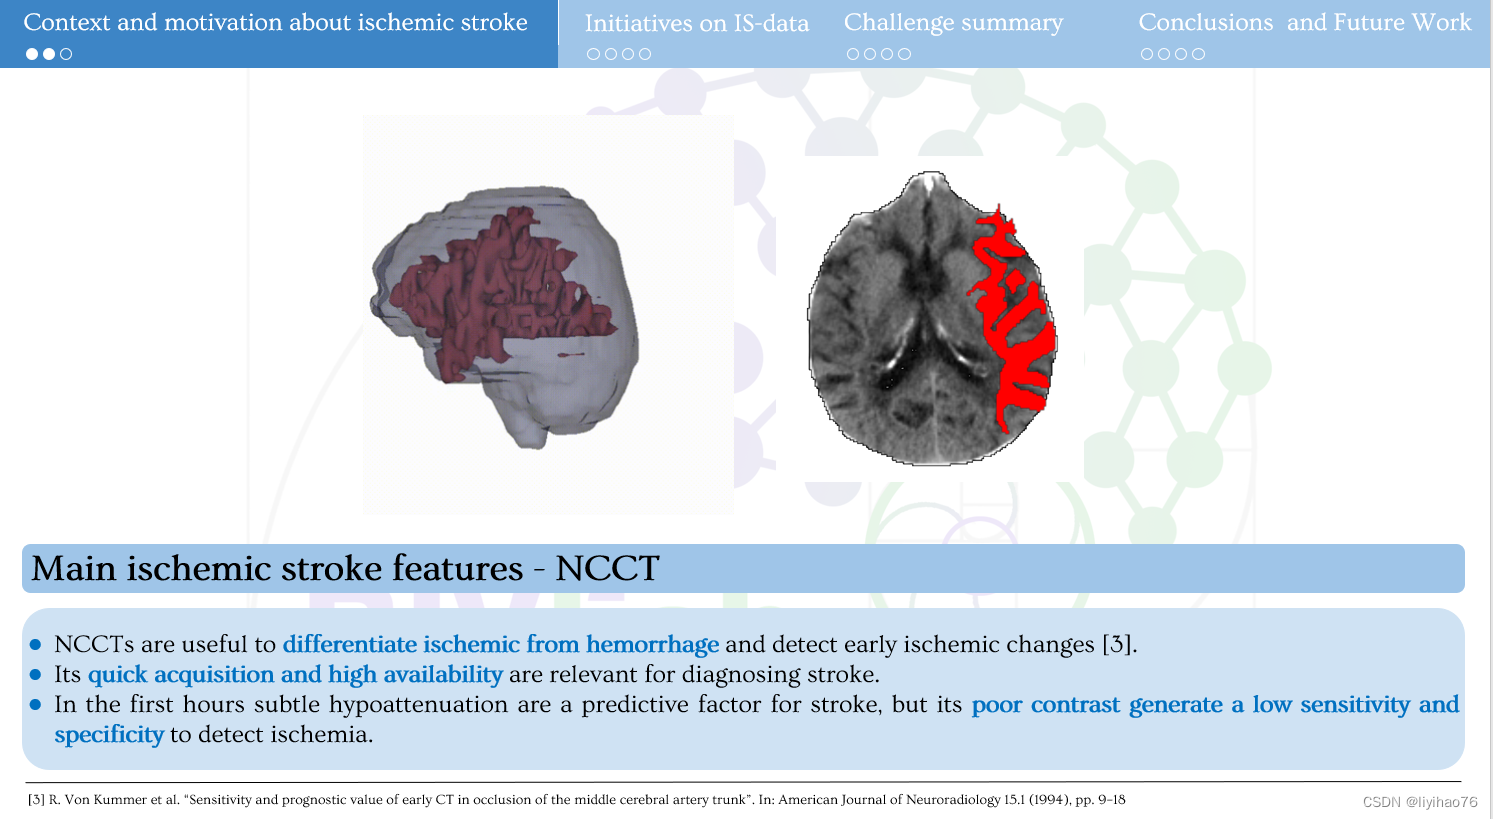

- NCCT

-NCCT 可用于区分缺血和出血并检测早期缺血变化 [3]。

-它的快速获取和高可用性与诊断中风有关。

-在最初几个小时内,细微的低衰减是中风的预测因素,但其对比度差导致检测缺血的灵敏度和特异性较低。